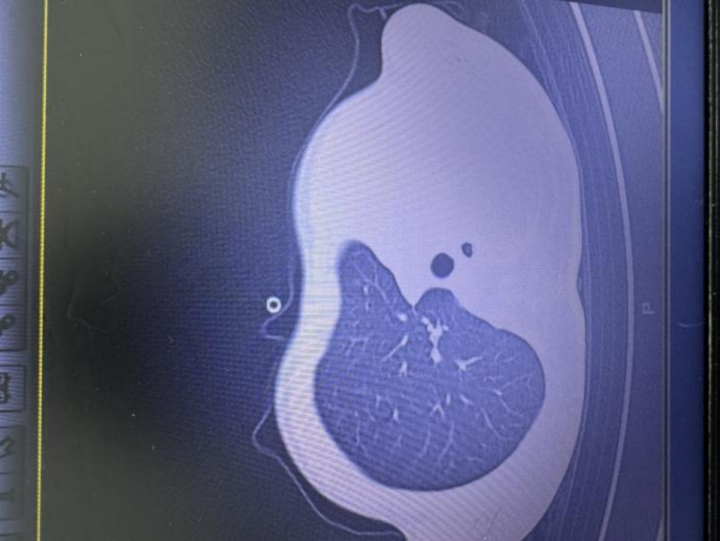

急診檢查結果讓醫護人員瞬間緊張:驗血顯示炎癥指標大幅上升,胸片更發現左側肺葉幾乎“不工作了,影像學中變成大片白色,即通常所說的“白肺”,意味著肺功能嚴重受損,孩子已經缺氧,隨時有窒息危險。

影像顯示肺白了一半